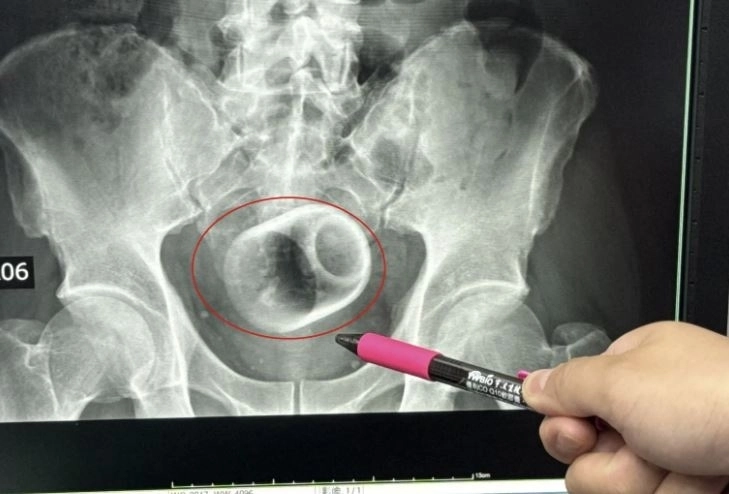

대만 타이중시 다자리 종합병원에서 X레이로 촬영한 남성 체내의 찻잔. 더 선 캡처

X레이 촬영 결과 그의 직장 안에 도자기 찻잔이 들어 있는 것으로 확인됐다. 찻잔의 크기는 폭 약 6㎝, 높이 약 8㎝였다.